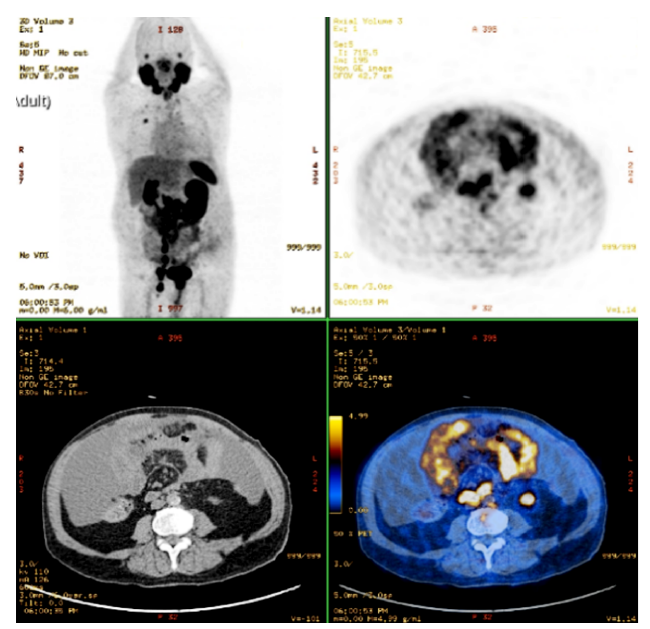

Figure 1: PET/CT with 68Ga-PSMA: The prostate shows high absorption without clear separation from the rectum, peritoneal effusion, scattered peritoneal thickening with heterogeneous uptake and multiple bilateral abdominopelvic adenopathies.